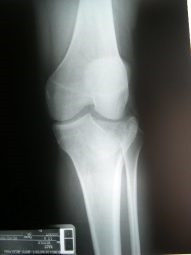

Fractura de plato tibial reducida bajo control artroscópico

Envíado por Dr. Luis Rodolfo Morales Choto